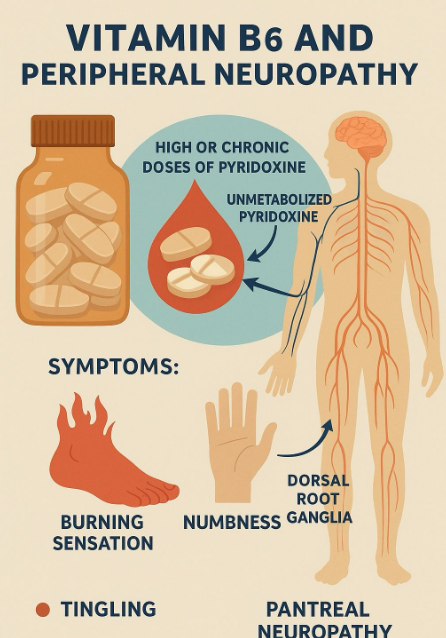

당뇨/알콜성 만성 췌장염 배경에서 결핵약 복용후 천천히 심해지다가, 급격한 증상을 호소하는 신경병증, 약제 관련? - 동대문구 답십리, 전농동, 우리안애 우리안愛 내과

한번 언급한 수개월의 가래가 폐결핵이었다? 배.. : 네이버블로그 상기 환자 약 6주뒤 내원 최근 아파서? 응급실만 수회 갔었다는데... 응급실만 5번 ***병원 - 진통제만 택시타고 **대 - 엑스레이, 진통제 **대 는 3번 간것 - 3번째 허리 MRI 회신서가 있어서 보니 ; 2일전 우측하지의 통증으로 응급실 내원, 허리 등에서는 통증의 원인이 없었던 분입니다. 당뇨병에 의한 마그네슘 부족으로 약제 처방하였으며.. 이후에 증상 호전되고 있습니다. ; 혈액검사 마그네슘으로 증상 설명을 하기엔?? lyribear cap 75 mg bid ultracet semi bid magnes tab bid ; 한달 처방 음주와 당뇨 문제가 있어 과거에도 발바닥 정도의 증상은 있었는데... 결핵약과 isoniazid 복용을 하고 있을테이니 참조하여 다시 문진을 해보면 ----->>>>> 7개월전 결핵약 처방받으면서 - 1주일 격리하고 퇴원했는데...